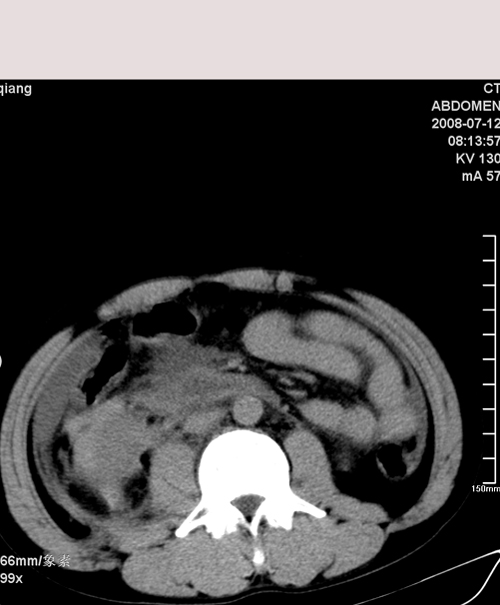

以下是引用muzi888在2008-7-15 10:45:00的发言:[br]大量腹腔积液,气腹,肾皮质弧形高密度影,诊断;1 空腔脏器穿孔 2 右肾包膜下血肿

以下是引用随光逐影在2008-7-15 11:18:00的发言:[br]考虑为:1)腹部空腔脏器穿孔。2)右肾破裂并肾包膜下血肿,肾盂积血。3)腹水(血)。